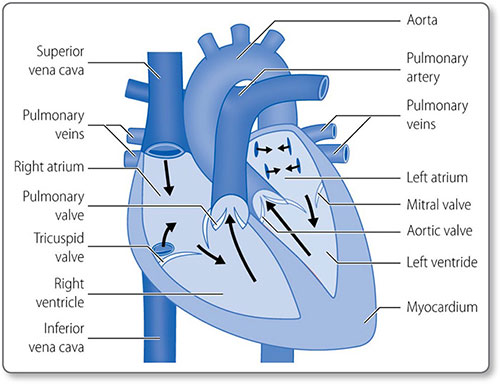

The heart is composed of muscle arranged around a framework of fibrous tissue and is the size of a fist. The two atria collect blood and fill the two ventricles, which pump blood into the pulmonary and systemic circulations (Figure 1.2). Its four valves prevent blood flow in the wrong direction.

Chambers and valves

The heart has four muscular chambers, each connected to a great vessel. The four valves lie between the ventricles and atria and the ventricles and the great arteries (Figure 1.5).

Left atrium

The mitral orifice and valve separate the left atrium and ventricle. The atrium receives its blood supply from the left circumflex coronary artery. The left atrial appendage or left auricle is a muscular out-pouching continuous with the left atrium. The left and right atria are separated by the interatrial septum.

Mitral valve

Left ventricle

Right atrium

Tricuspid valve

Right ventricle

Pulmonary valve